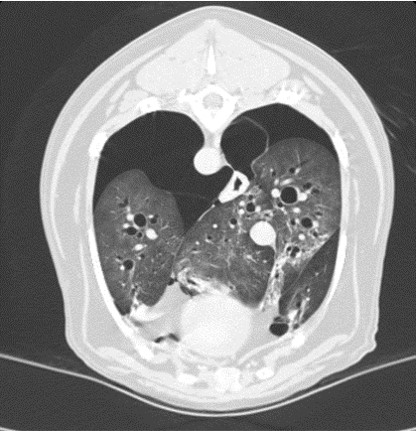

CT 검사

CT는 신체의 여러 각도에서 x-선을 투과시킨 후 단면 영상과 3차원적 입체영상을 얻을 수 있어 해부학적 구조와 병적 변화 정도를 정확하고 빠르게 평가할 수 있습니다.

CT 검사는 각종 종양과 염증, 외상 및 신체 기형과 같은 질환의 진단에 유용하게 사용될 수 있으며 수술이 지시되는 경우에도 진단을 넘어 정확한 해부학적 구조의 평가가 가능해져 이를 통해 수술 계획을 수립할 수 있습니다.

건국대학교 동물암센터에서 보유하고 있는 CT는 여러 개의 디텍터를 갖고 있는 multi-detector CT (MDCT)로써 촬영 시간 및 피폭량을 최소화 할 수 있는 장점이 있습니다. 여러 개의 디텍터를 통해 선명한 영상을 빠르게 구현해 냄으로써 진단의 정확성을 높일 수 있습니다.

대표질환

- 종양 진단 (두경부, 흉강, 복강, 사지 골격) 및 전이 평가

- 폐 질환

견갑골 종양 -

기흉 -

전신문맥단락(PSS)